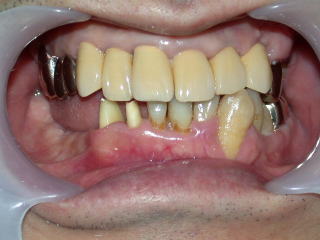

インプラント症例1

43歳男性

初診時平成17年8月

虫歯も歯石もひどく、歯肉は炎症を起こし、口腔内状態は劣悪でした。

保険内診療で歯石を取り、保存不可能な歯を抜歯し、詰め物、かぶせ物も終わりました。

約半年後の平成20年2月、右下に入れ歯を作るところまで診療が進みました。

患者さんから入れ歯はいやなのでインプラントにしたいとの申し出がありました。

抜歯した穴も十分治り、仮歯、インプラント植立の固定用仮歯の用意もでき、次回インプラント植立します。

患者さんの希望により全部セラミックスの白い歯を入れることになりました。